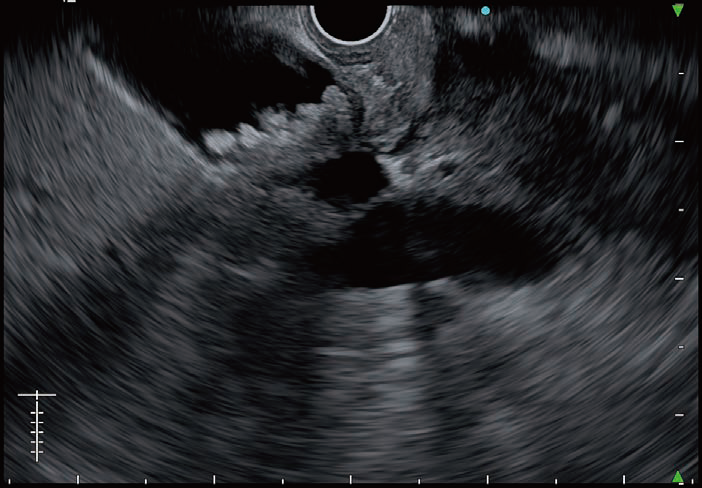

FNA/FNB needles under ultrasound image by EU-ME3 is clearly visible. We did several EUS-FNA/FNB procedures in pancreas and lymph nodes, and could identify the target lesion, needle and any structures in between more clearly compared to EU-ME2. Different sizes of needles were used for EUS-FNA/FNB and we can confirm that there was no noticeable deterioration of needle visibility even with smaller size of needles. The images on the right show Olympus FNB Needle, EZ Shot 3 Plus by different sizes (19G, 22G and 25G), under B-mode or THE-P mode of EU-ME3 during FNB procedures. Needle visibility under EU-ME3 is excellent and it can be seen end-to-end clearly even for 25G needle size. This end-to-end needle visibility helps to make EUS-FNA/FNB procedures safer with accurate targeting, supporting physicians to be more confident on making decisions. While using doppler functions, like color doppler, power doppler or H-flow, resolution of the image remains good without lag which possibly is because of high frame rate of EU-ME3.